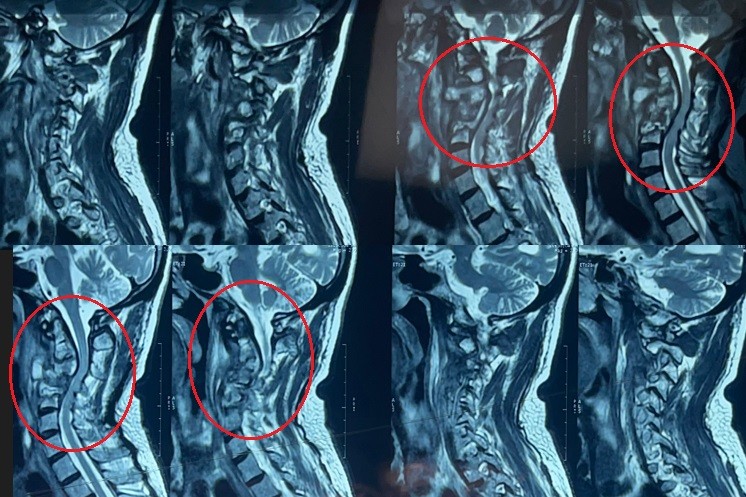

cervical vertebrae kyphosis repair